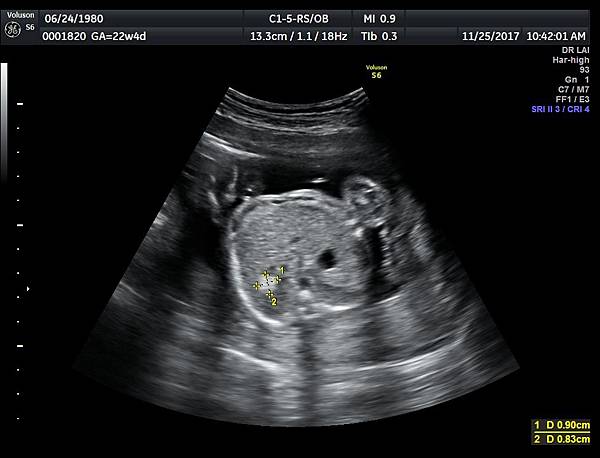

孕兒診所備忘錄 307 suspect fetal liver hemangioma images

suspect fetal liver hemangioma images